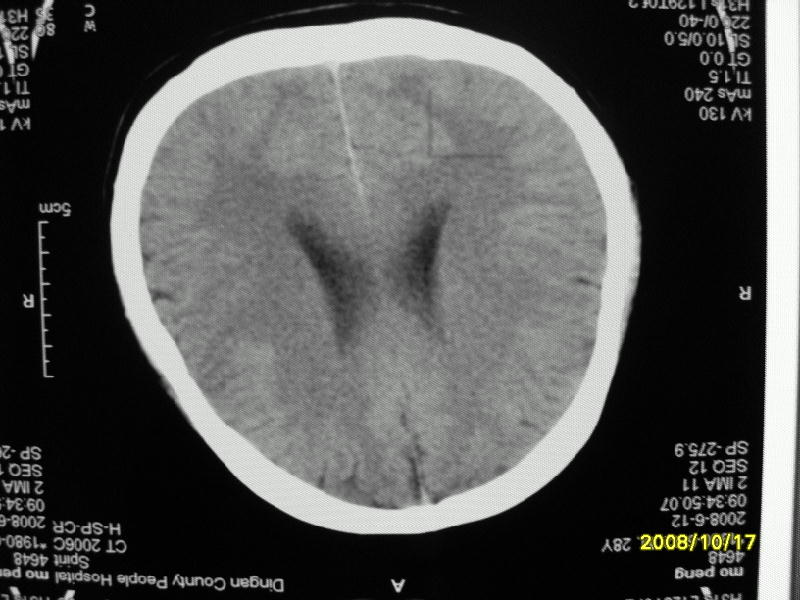

检查名称:     ct颅脑平扫           男     28岁

表现:左顶叶见斑点状致密影。边缘清,大小约0。3*1。0cm,余脑实质密度及灰白质结构示见异常。脑室系统大小,形态,密度未见异常。脑沟。脑裂。脑池未见异常密度影。中线结构无移位。

印象:左顶叶少许钙化灶

左顶叶见斑点状致密影。边缘清,大小约0。3*1。0cm,余脑实质密度及灰白质结构示见异常。脑室系统大小,形态,密度未见异常。脑沟。脑裂。脑池未见异常密度影。中线结构无移位。

印象:左顶叶少许钙化灶。

左顶叶见斑点状致密影